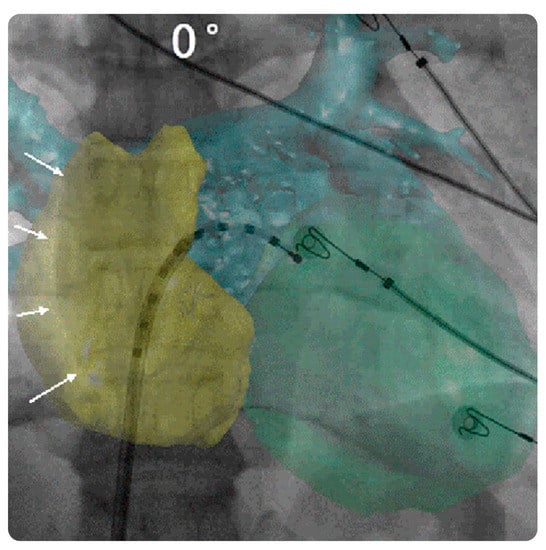

3.2.1. StentBoost Live

This live-imaging medical device assists physicians in placing and deploying stents by providing an inclusive visualization of stents in coronary vessels. It allows for procedural efficiency with enhanced visualization during intracoronary device movement and can be consistently integrated into standard-of-care workflows for optimized percutaneous coronary intervention (PCI). StentBoost Live can be used simultaneously with Philips Interventional X-ray software. A PACS system must be operated when using StentBoost Live [28,29,30,31] (Figure 5 and Figure 6).

StentBoost Mobile

This is the first dedicated stent-imaging software for mobile C-arm segments. It enables enhanced stent visualization during deployment for better decisionmaking during endovascular treatment and other vascular procedures. It also expands the assessment potential, saves time and money, and supports various vascular interventions [28,29,30,31] (Figure 5 and Figure 6).

Figure 5. StentBoost Live software and its role in the delivery of targeted therapy. (a) Standard static road map with contrast media. (b) Coronary road map fused with live fluoroscopy image showing both wires exactly superimposed on the coronaries. (c) The software algorithm automatically searches for proximal and distal balloon markers and displays an enlarged and enhanced image of the area around them to insure precise balloon-mounted stent deployment. Reprinted from “On the road: First-in-man bifurcation percutaneous coronary intervention with the use of a dynamic coronary road map and StentBoost Live imaging system” by Dannenberg et al. [32] with written approval from the corresponding author and publisher (International Journal of Cardiology; Copyright 2016).